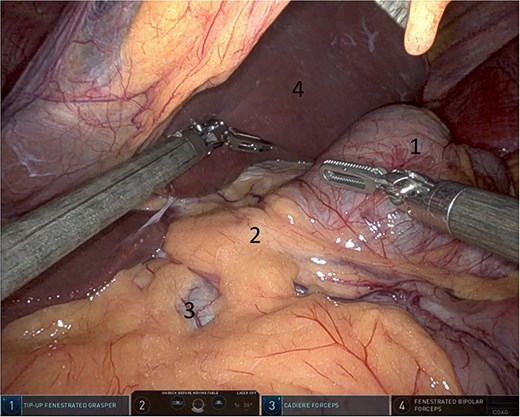

Upon entering the abdominal cavity, dilated bowel loops were observed (Fig. 2), and a significant portion of the colon was found herniated through the foramen of Winslow (Fig. 3). The herniated colon was covered by the pars flaccida (Fig. 4) (Video S1). Careful dissection was performed anterior to the hepatoduodenal ligament (Fig. 5). The gall bladder was retracted to the patient's right upper quadrant, which allowed for the retraction of the foramen of Winslow (Fig. 6) (Video S1). After carefully placing the tip of the instrument posterior to the portal vein and gently elevating it, the herniated colon was successfully reduced (Fig. 7) (Video S1).

Gallbladder was retracted to the patient's right upper quadrant which allowed for the retraction of the foramen of Winslow and anterior mobilization of it (1: gall bladder, 2: herniating colon, 3: first part of the duodenum, 4: portal vein).